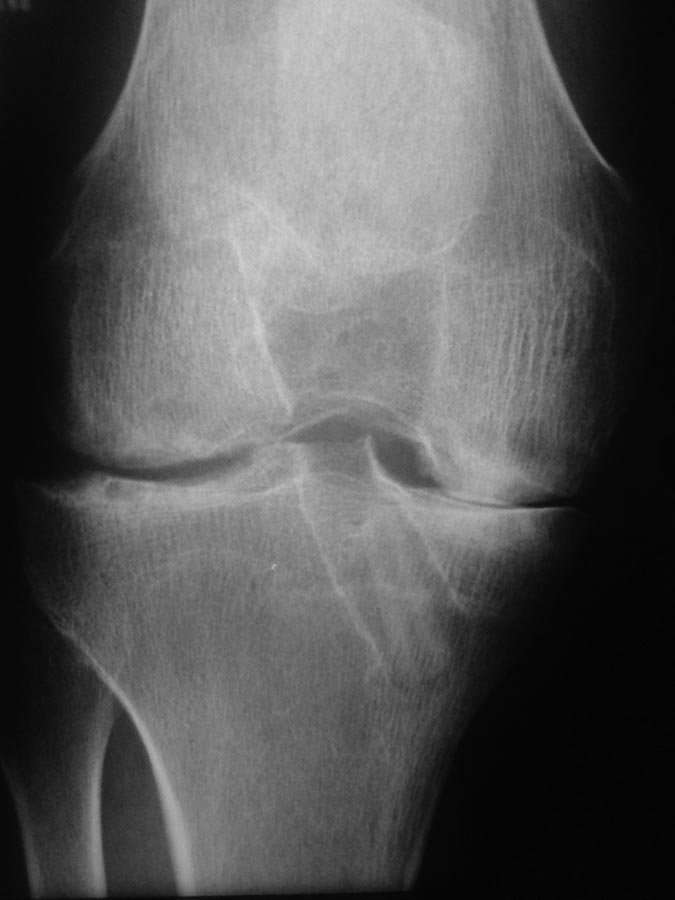

[Ortho] Артроз ?

Доброго времени суток, коллеги. Прошу помощи, совета по данному

случаю: Пациент 20 лет, обратился с болями в коленном суставе.

усиливающимися при физических нагрузках, крепитацию сустава.

На сегодняшний  момент: поступил с болями в суставе, крепитацию,

ограничение ф-ии, мышечную гипотрофию. В периоде реабилитации (в течении

данного года) не исключает тяжелые аксиальные нагрузки. Травм не было.

Температура тела не поднималась. Другие суставы не беспокоят. Осмотрен

ревматологом- ревмо патологии нет, туберкулез отрицает.

Локально- мышечная гипотрофия, сустав не отечен, при пальпации

болезненность по всем отделам, при движениях боль и выраженная крепитация.

Согласно всему изложенному выполнена диагностическая артроскопия-

синовия в переднем завороте гиперемирована не гипертрофирована, местами

отложения (еденичные) по типу мелких хондройдов. Медиальный компартмент-

тотальные хондромаляции 3-4ст, местами участки хрящевой ткани по типу

"островков", мениск дегенеративно изменен. При осмотре латерального

компартмента- картина аналогична. При осмотре ПКС , по передней

поверхности ее разростание соединительной ткани, массивный стеноз

овального отверстия. Выполнена гистология из различных участков и

фрагментов.

Рентген динамика за год резко отрицательна.

Уважаемые коллеги, ЧТО могло так патологически и  очень быстро

повлиять на развитие артроза и артроз ли ЭТО. За все мнения, советы,